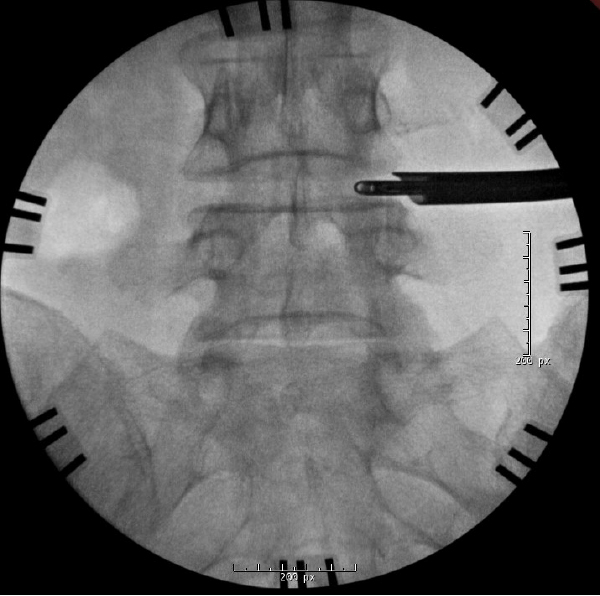

Intraoperative AP fluoroscopy demonstrating targeting through Kambin’s triangle